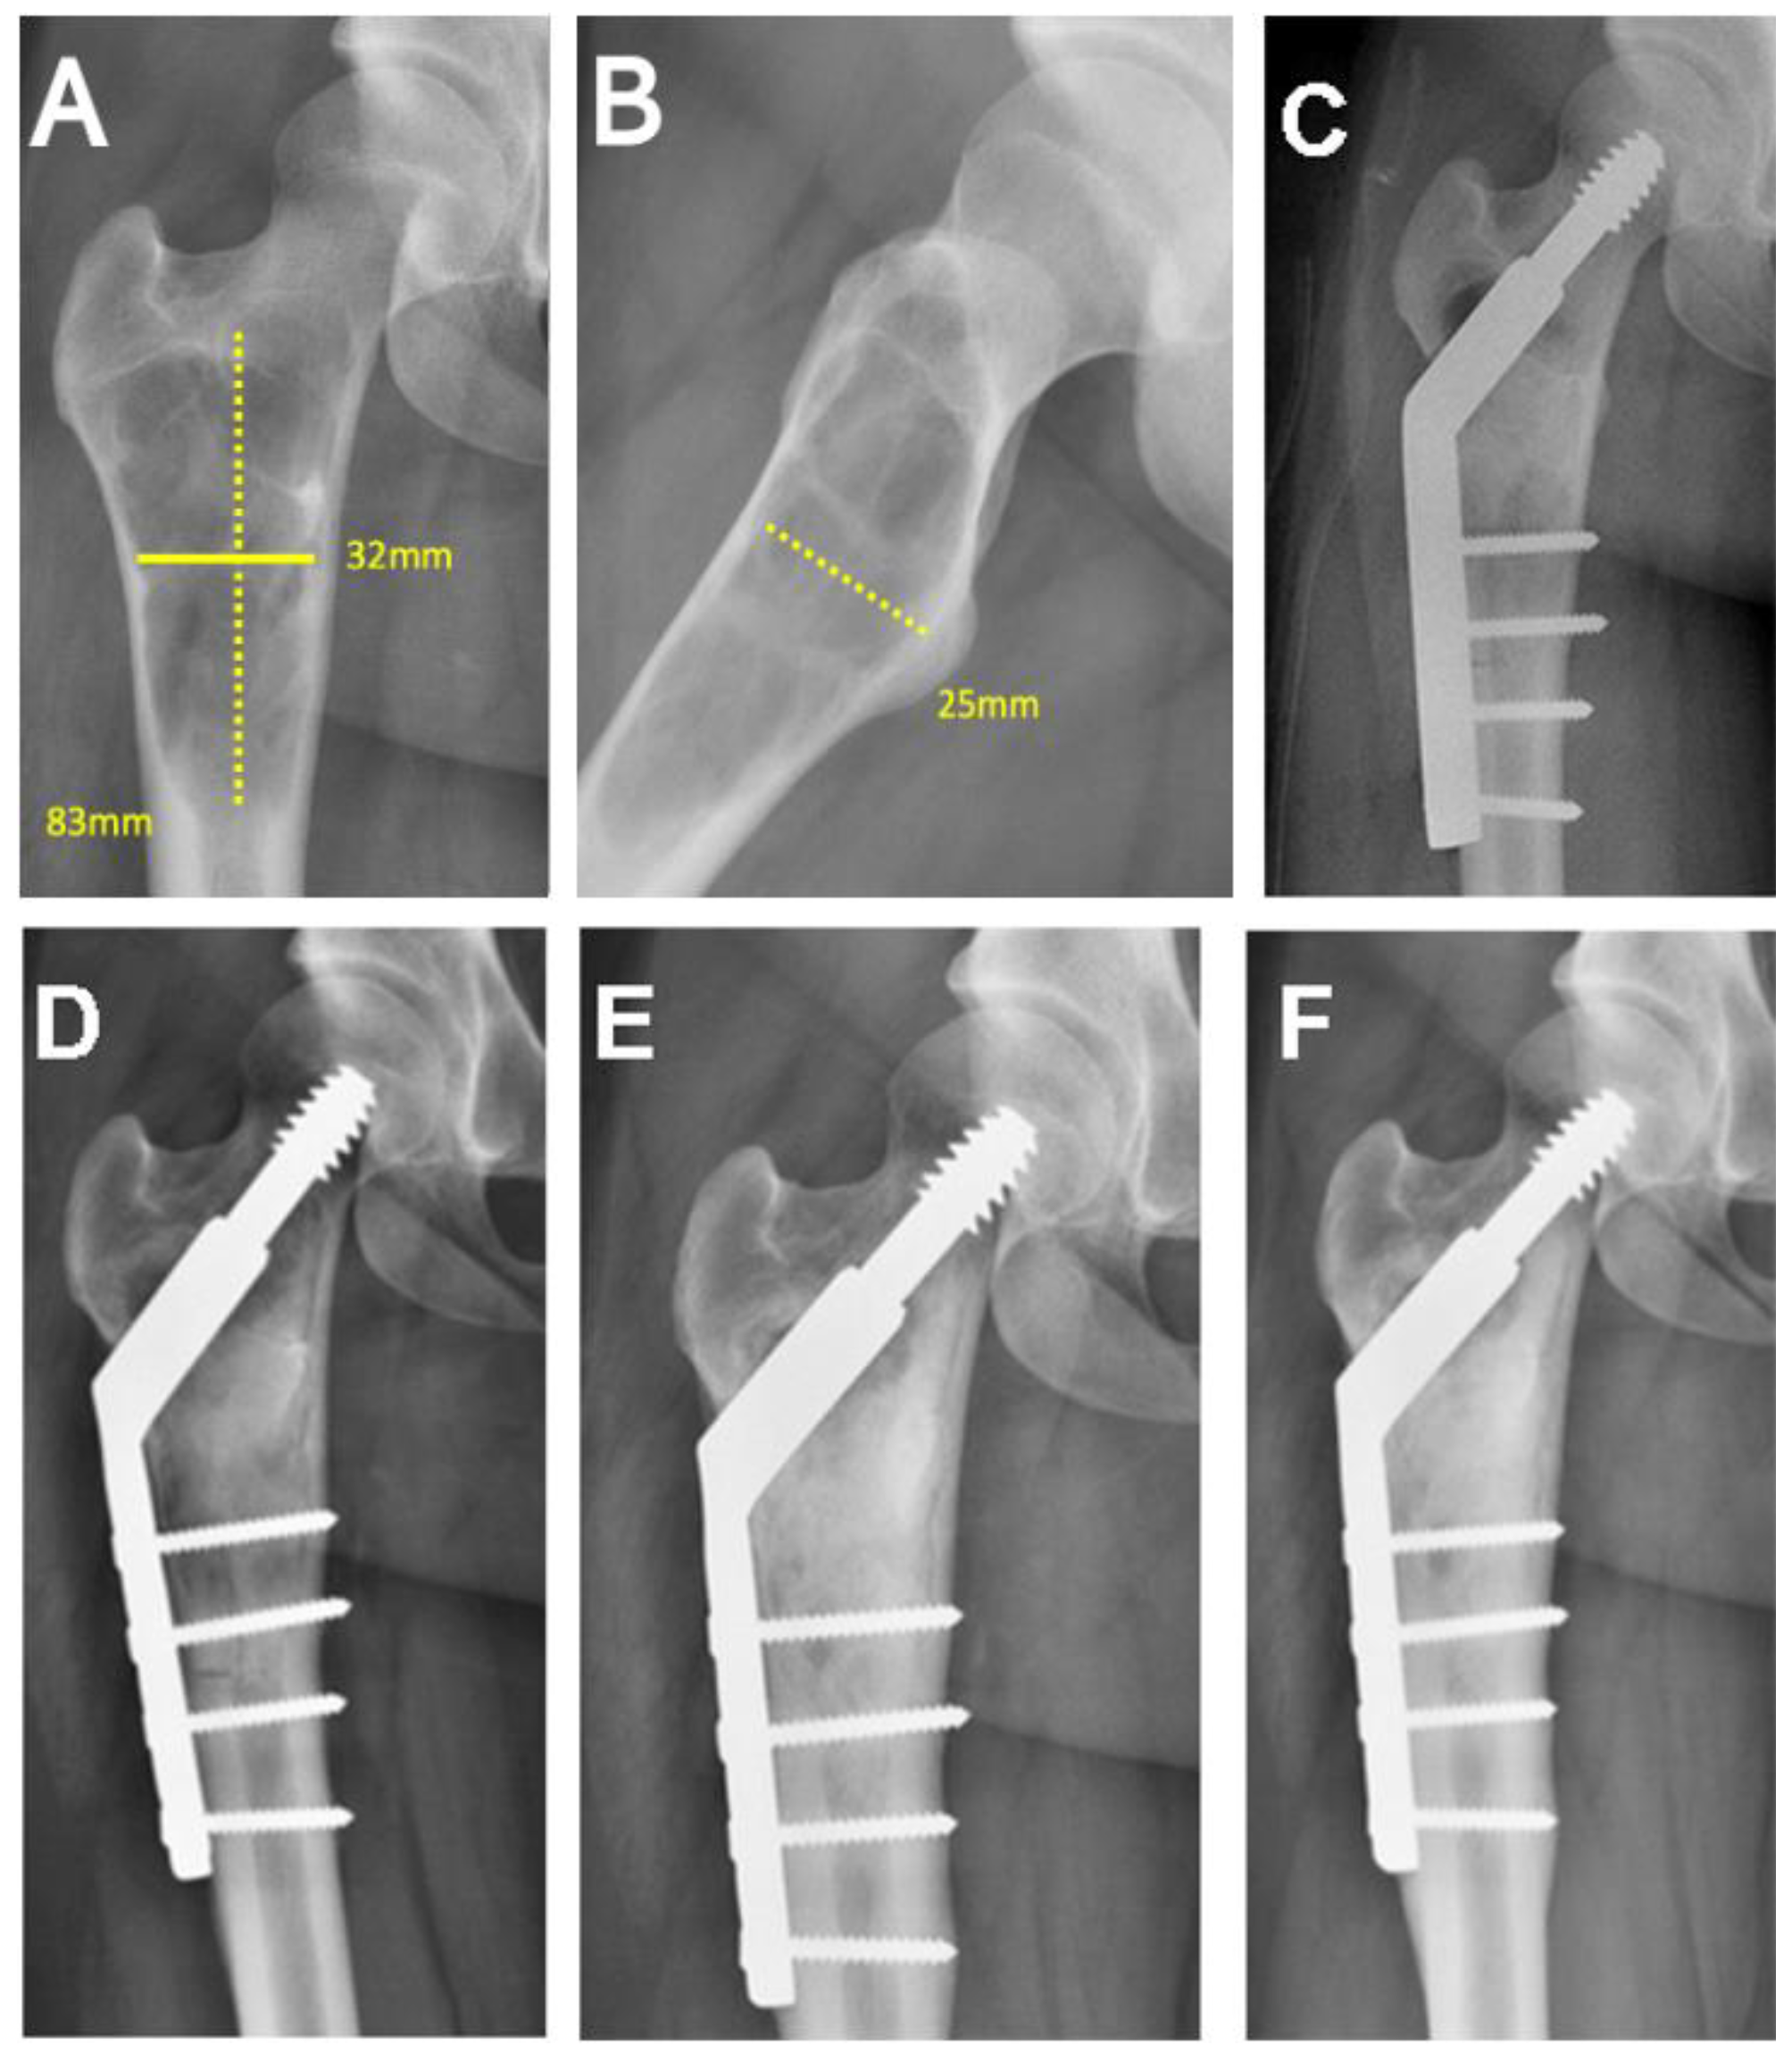

| 24/M/38 | Proximal femur | Simple bone cyst | 101.42 |